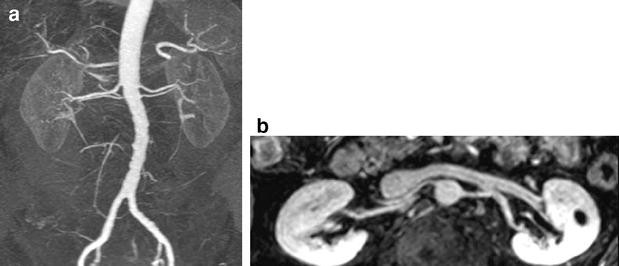

In the imaging protocol, special attention should be focused on arterial and venous imaging, in addition to the standard parenchymal imaging. For the arterial MR angiography, a 3D fast GRE with intravenous gadolinium after timing bolus can be used (TR 4.7 ms, TE 1.4 ms, flip angle 30°), with coronal thin-section reconstructions. A relatively large flip angle (up to 40°) can be used to minimize background signal around the high signal of the renal arteries [56]. The venous angiography sequence should follow the arterial angiography immediately. Due to the excretion of gadolinium by the kidneys, the concentration of gadolinium in the renal veins is lower than in the renal arteries, causing lower contrast of the veins compared to the background. A lower flip angle (15°) can be used to compensate for the lower gadolinium concentration, at the expense of more background signal [56]. The 3D dataset can be used for the reconstruction of thin 2D sections for detailed evaluation, as well as for maximum intensity projection (MIP) reconstructions of the vessels (Fig. 8).

Pre-operative imaging of potential donor kidneys. a Gradient echo image after intravenous contrast, arterial phase, TR 3 ms, TE 1 ms, slice thickness 2.2 mm, flip angle 27°, coronal. b Gradient echo image after intravenous contrast, nephrographic phase, TR 4 ms, TE 1 ms, slice thickness 2.2 mm, flip angle 15°, coronal. The lower flip angle in the depiction of the renal veins was chosen to compensate for the lower gadolinium concentration in the renal veins